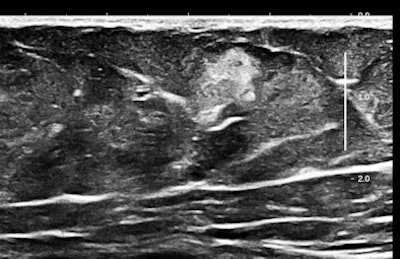

Here are three representative (HD) anterior abdominal wall images at 15 MHz:

Mast cells and mediator-release disorders

These echogenic "nodules" are tumorlike collections and cellular infiltrates of mast cells. The precise diagnosis is systemic mast cell disease. Symptoms are due to mediator release. At one pole is typical carcinoid syndrome involving serotonin and kallekrein, and at the other extreme is anaphylaxis with predominant histaminelike substances. Because of the large number of nodules, there is a significant neuroendocrine burden, similar to the multiple metastases of a malignant carcinoid tumor filling the liver.

Soft, well-demarcated reflective nodules in subcutaneous fat are an Aunt Minnie of a sign. They are not palpable, and I suspect they can only be found by high-frequency ultrasound, which is perfect for outpatient screening applications. There may be a completely unexpected, relatively high prevalence of this finding, and it seems that multiple nodules may predispose several allergic disorders, including conditions such as irritable bowel syndrome (IBS), fibromyalgia, and possibly even exercise-induced asthma or postexertional hypotension and reactive tachycardia.